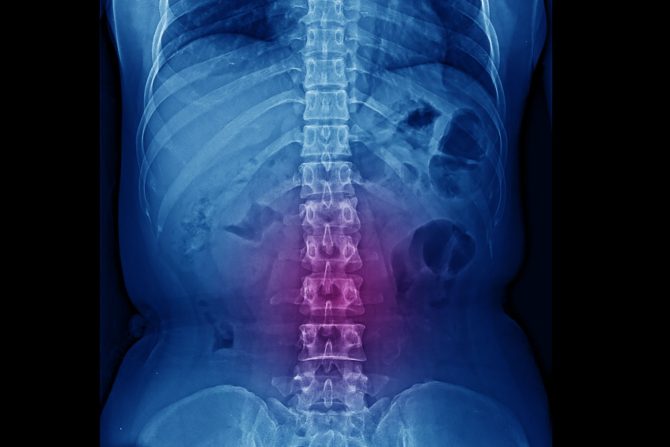

Kompresija kičmene moždine dešava se kod otprilike 5 odsto onkoloških pacijenata, kada se metastaze pojave na kostima kičme. Najčešće do toga dolazi kod primarnih tumora dojke, pluća, prostate i neuroblastoma (kod dece).

Maligne ćelije u leđima odnosno kičmi mogu da izvrše pritisak na kičmenu moždinu i tada dolazi do kompresije kičmene moždine. Jedan od najranijih simptoma ovog stanja je bol u leđima ili vratu. Veoma je važno odreagovati blagovremeno jer zbog kompresije kičmene moždine može doći do paralize. Ukoliko su pogođene noge osoba ne može da hoda, a ako tumorska tvorevina pritiska kičmenu moždinu u vratu, oduzimaju se ruke i noge. Na kompresiju kičmene moždine mogu da ukažu sledeći simptomi:

Oko 90 odsto slučajeva kompresije kičmene moždine nastaje širenjem metastatskog tumora. Najčešće prethodno biva zahvaćen neki od pršljena.  Kičmena moždina je tada izložena direktnom pritisku a onda demijelinizaciji i oštećenjima. Posledično, dolazi do kompresije krvnih sudova, ishemije i edema. U slučaju limfoma, na primer, maligne ćelije mogu da uđu u epiduralni prostor i uzrokuju oštećenja urastajući u vertebralne otvore i bez razaranja pršljenskog tela. Međutim, većina tumora ostaje u epiduralnom prostoru.

Postavljanje dijagnoze počinje RTG snimkom kičme, koji u čak 90 odsto slučajeva potvrđuje sumnju na patološke promene. CT (skener) je senzitivnija metoda od standardne radiografije i preporučuje se. Kod sumnje na maligne lezije u kičmenoj moždini, metoda izbora je magnetna rezonanca (MRI).